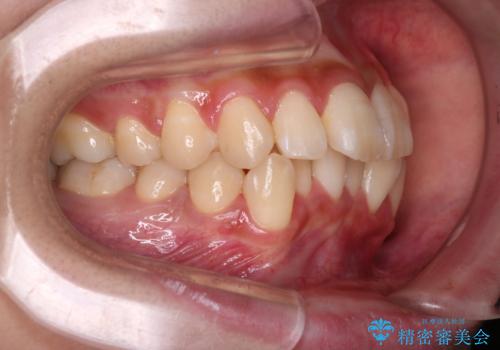

反対咬合を治したい。インビザライン

- 前歯の反対咬合を治したいことを主訴に来院されました。

インビザラインにて臼歯の遠心移動を行いながら、スペースを作り反対咬合を改善することができました。